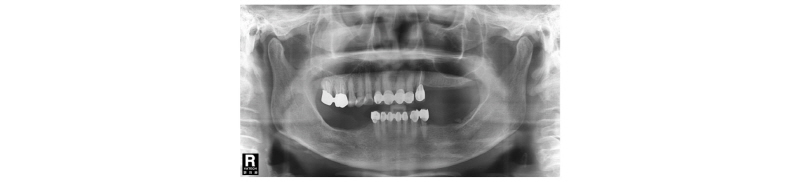

57세의 여성 환자로 기존 브릿지 보철 수복물(#24-27)의 상악 좌측 제 2대구치의 심한 우식으로 인해 내원하여 해당 치아를 발거하였다(Fig. 1). 상악 좌측 제 1 소구치는 근관치료를 시행한 후 보철 수복하기로 하였고 기존 pontic 부위였던 좌측 제 2 소구치와 발거된 제 2 대구치 부위에 #25i, #27i 2개의 임플란트 식립을 통한 브릿지 보철 수복물을 계획하였다(Fig. 2). 기존 pontic으로 유지되었던 좌측 제 2 소구치 부위는 치조제의 심한 수평적 치조골 흡수를 구강 내 임상검사를 통해 확인할 수 있었다. 전층 판막 형성후 상악 좌측 제 2 소구치 부위의 치조정 폭경은 약 2 mm 정도로 측정되었다(Fig. 3, 4). 치조골의 구개측에 약 1 mm의 치조골이 남도록 high speed carbide round bur를 이용하여 치조정에 horizontal intraosseous groove를 형성하였고 협측골의 근심, 원심측에 2개의 vertical intraosseous groove를 형성하였다(Fig. 5). Chisel과 ridge spreader drill (RS kit, Dentium, Korea)을 이용하여 점차적으로 협측 골판을 구개측으로부터 분리시켰다(Fig. 6). Osteotome을 이용, 식립 깊이까지 적용하여 임플란트 식립 부위를 형성하였고 Ø4.3 × 10 mm (Implantium, Dentium, Korea) 임플란트를 식립하였다(Fig. 7). 발치 후 치유된 상악 좌측 제 2 대구치 부위는 상악동 거상술(수직 접근법)을 시행, 골이식을 한 후 4.8 × 10 mm (Implantium, Dentium, Korea)를 식립하였다(Fig. 8). 이후 이종골 이식재(Bio-Oss®, Geistlich, Switzerland)를 식립된 임플란트와 협,구개 측 치조골판 사이의 gap과 협측골판 상방에 적용하고 흡수성 교원질 차폐막(Bio-Gide®, Geistlich, Switzerland)로 피개한 다음 감장절개를 통해 장력없이 봉합하였다(Fig. 9-11). 이후 구강 내 검사 및 방사선 검사를 통해 수술부위 치유상태를 확인하였고 특이한 임상적 소견없이 정상적으로 잘 치유되었다(Fig. 12). 약 3개월 10일 정도의 치유기간 후 이차수술을 시행하였다(Fig. 13). 판막 거상 후 치조제 분할술을 시행하였던 상악 좌측 제 2 소구치 부위에 잘 형성된 신생 골양조직이 관찰되었다(Fig. 14). 상악 좌측 제 2 소구치 부위와 상악 좌측 제 2 구치 부위에 치유지대주를 장착하였고 상악 좌측 제 1 대구치 부위에 추가적으로 임플란트를 1회법으로 식립하였다(Fig. 15). 이차수술 이후 정상적으로 치유가 진행되어 약 2개월 후 최종 보철물 수복을 하였다(Fig. 16, 17). 약 1년 정도의 follow-up시 구강 내 검사와 방사선 검사를 통해서 임플란트 주위 연조직과 변연골이 잘 유지되고 있음을 확인하였다(Fig. 18).

|

Fig. 1. First visit. Panoramic x-ray view. |